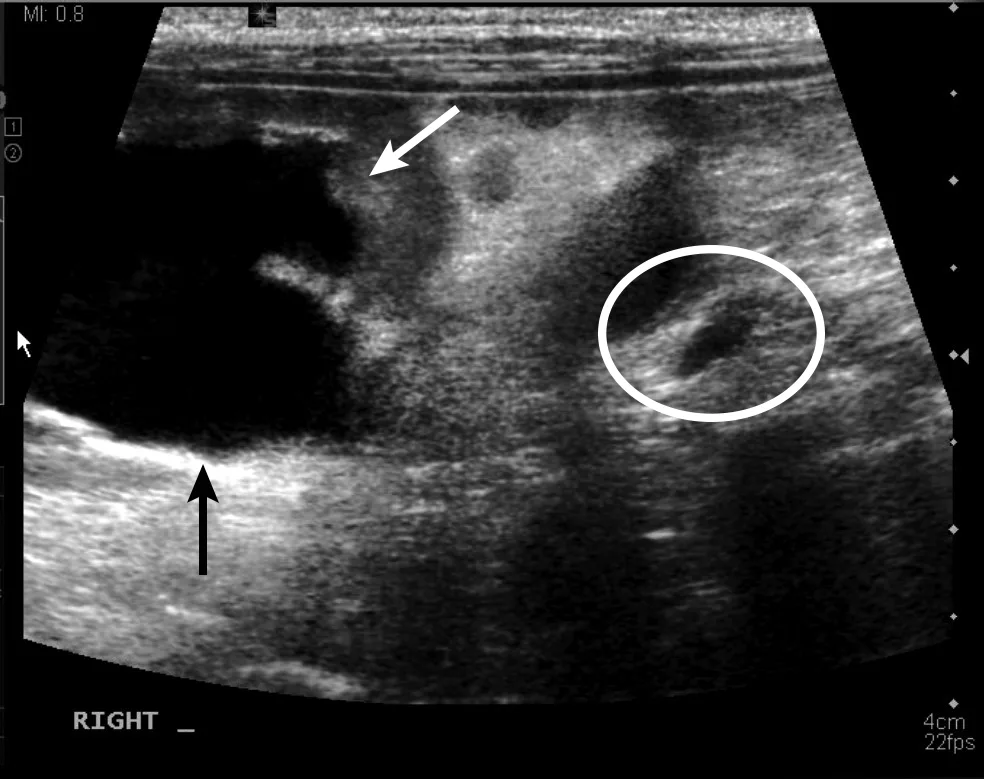

Urinary bladder masses (generally transitional cell carcinoma [Figure 5], but adenocarcinoma or rhabdomyosarcoma are also possible7-9) can cause hematuria or stranguria. On ultrasound, these masses are typically luminal and multilobulated, with rhabdomyosarcoma having a grapelike (ie, botryoid) appearance.7,9 Mineralized urinary bladder masses (rare) are usually urethral transitional cell carcinoma or prostatic adenocarcinoma that locally spreads into the urinary bladder. These masses can occupy the trigone region and occlude the ureters, causing secondary hydronephrosis (Figure 6).8

Sagittal image of the urinary bladder with 2 masses (arrows) along the ventral wall (one at trigone level) in a dog with transitional cell carcinoma. Left, cranial; bottom, dorsal

Sagittal image of the caudal aspect of the right kidney, showing severe dilation of the renal pelvis (arrows) and dilation of the ureter (circle) just caudal to the kidney caused by the transitional cell carcinoma seen in Figure 5. Left, cranial; bottom, dorsal